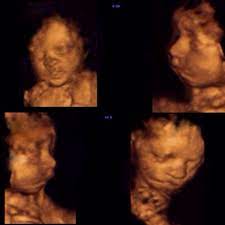

3d Image Of Baby At 27 Weeks Images Poster

3d Image Of Baby At 27 Weeks Images Poster from i.pinimg.com